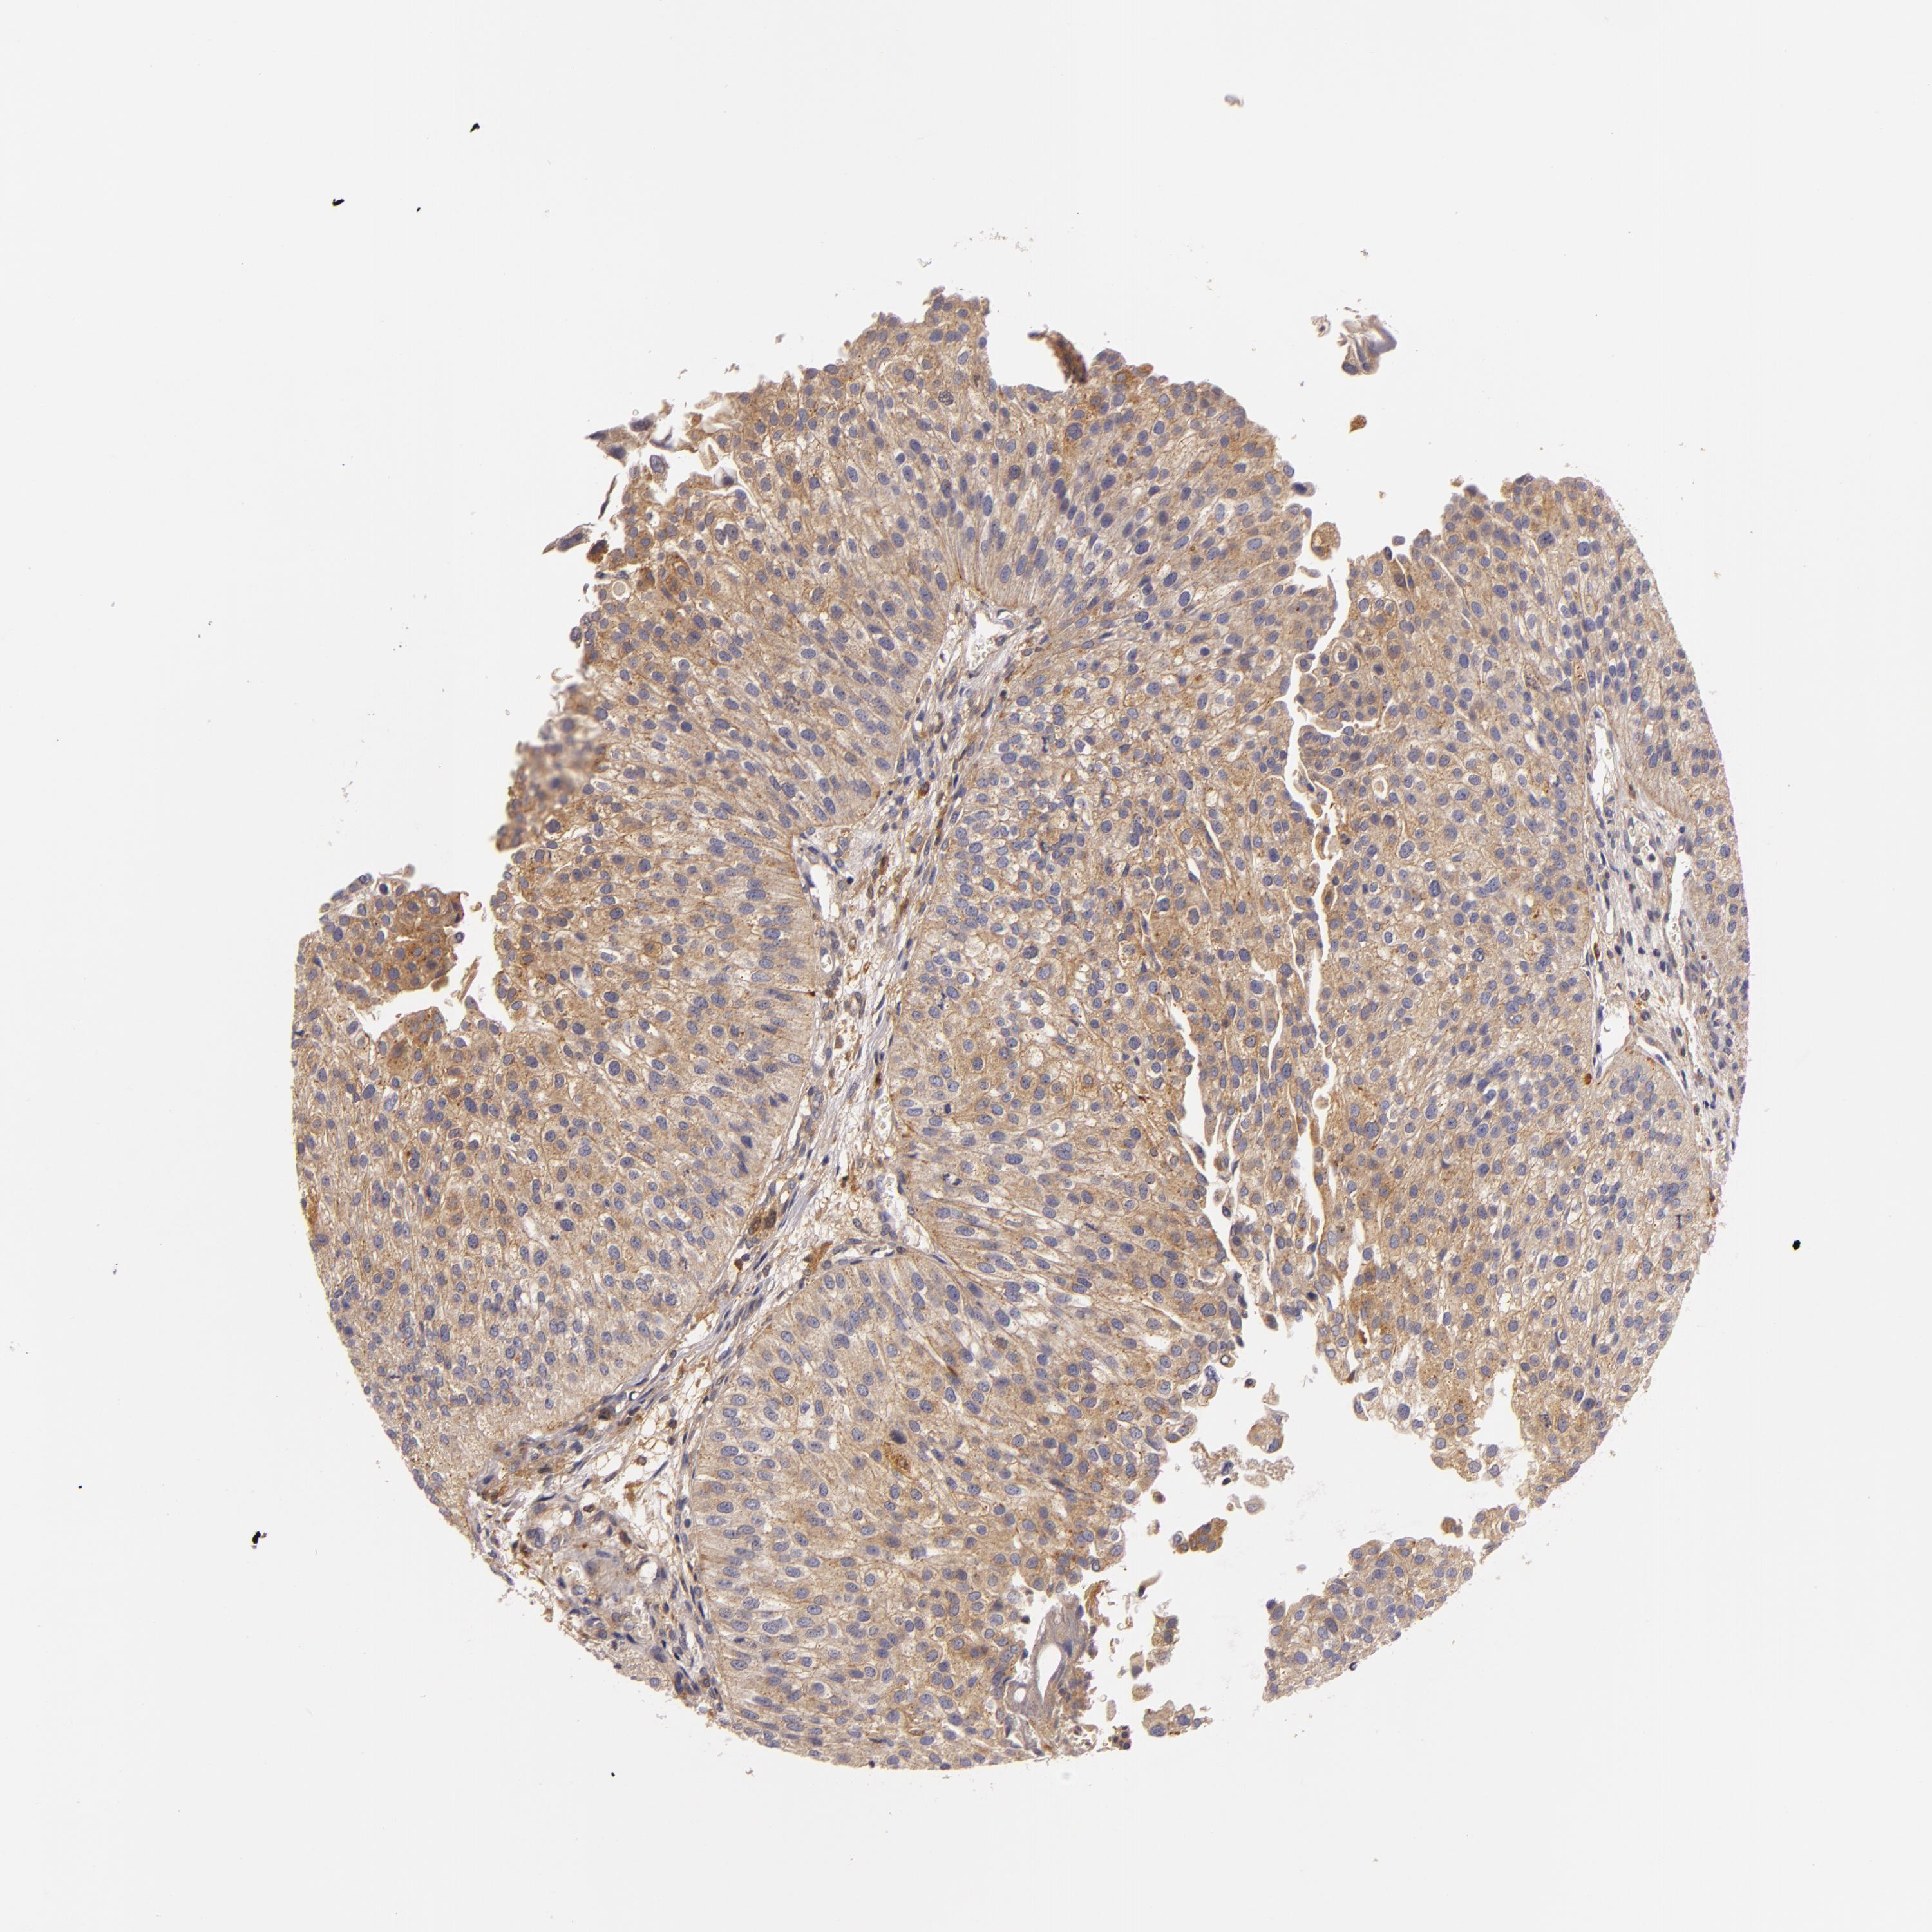

UROTHELIAL CANCER - Protein expressioni

A mouse-over function shows sample information and annotation data. Click on an image to view it in a full screen mode. Samples can be filtered based on level of antibody staining by selecting one or several of the following categories: high, medium, low and not detected. The assay and annotation is described here.

Note that samples used for immunohistochemistry by the Human Protein Atlas do not correspond to samples in the TCGA dataset.

Antibody stainingi

Antibody staining in the annotated cell types in the current human tissue is reported as not detected, low, medium, or high, based on conventional immunohistochemistry profiling in selected tissues. This score is based on the combination of the staining intensity and fraction of stained cells.

Each image is clickable and will lead to virtual microscopy that enables deeper exploration of all samples and also displays staining intensity scores, fraction scores and subcellular localization as well as patient and tissue information for each sample.

Antibody HPA001749

Urothelial carcinoma, High grade

Urothelial carcinoma, Low grade